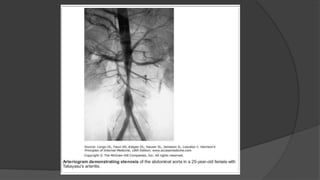

2. TAKAYASU ARTERITIS

 Takayasu arteritis is an inflammatory and stenotic disease of medium

and large-sized arteries characterized by a strong predilection for the

aortic arch and its branches.

 The involvement of the major branches of the aorta is much more

marked at their origin than distally.